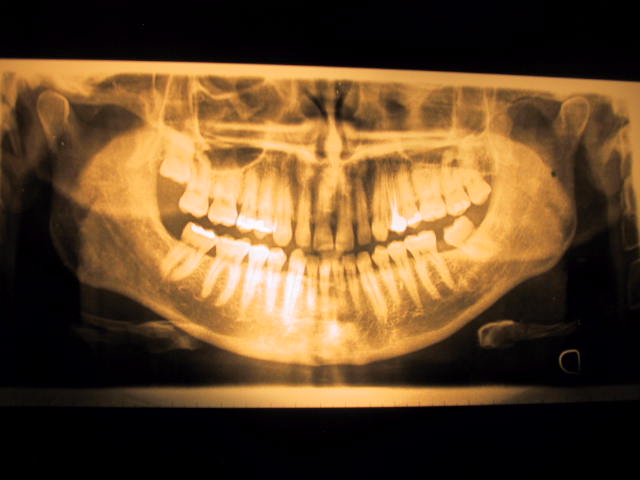

Iniziamo dall' ultima domanda: si, esiste una precisa correlazione tra postura e dentatura, in quanto l'articolazione temporo-mandibolare (e di conseguenza l'occlusione tra le arcate dentarie) rappresenta l'"estremo cefalico", mentre l'appoggio plantare a terra rappresenta l'"estremo podalico" riguardo la posizione del corpo nello spazio, cioè la postura. Non esiste un solo esame specifico per la verifica di ciò, ma un'intera branca scientifica che si occupa della posizione e del movimento del corpo. In riferimento alla sua attenta descrizione sintomatologica, sovrapponibile agli effetti che ci si potrebbe aspettare da quel che si vede con la rx-panoramica, il mio consiglio è di togliere i denti del giudizio superiori, che le causano una contrazione isometrica muscolare (temporale e massetere), e di eliminare il precontatto causato dall'inclinazione del molare del giudizio inferiore destro. Intervenire poi con correzione ortodontica del morso coperto. Un bravo ortognatologo potrà aiutarla!

Sono daccordo con tutte le teorie (ascendenti, discendenti, ecc), e, naturalmente, il caso necessita di ulteriori indagini. Voglio solo dire che ho avuto un caso simile lo scorso anno che ho risolto semplicemente raddrizzando un molare inferiore mesializzato...come quello nella foto. Sparito il CLICK, spariti gli acufeni. Tanto vale provare!

Gentile paziente, lei HA DESCRITTO i sintomi di una malocclusione, pur affermando che non c'è malocclusione. Guardando la lastra si nota la mancanza di un primo molare inferiore, con conseguente spostamento in avanti e inclinazione del molare dietro. I denti magari saranno anche allineati, ma ciò non vuole assolutamente dire che "si muovano" correttamente quando lei parla, mastica, deglutisce... Potrebbero (e probabilmente è così) non ingranare bene fra di loro, come due ruote dentate che non si accoppiano perfettamente l'una all'altra. Ogni arcata in sostanza è a posto, ma messe insieme spingono i condili della mandibola in posizione anomala. Di qui i disturbi. Un bite fatto "a casaccio" della serie "vediamo se funziona" non mi sembra la soluzione più appropriata. ------------------------------------------------------------------------ Cosa fare allora? In primo luogo una VISITA da una persona competente in DISFUNZIONI DELL'ARTICOLAZIONE TEMPORO-MANDIBOLARE, uno GNATOLOGO in altre parole. Lui è lo specialista giusto; può essere un dentista con una particolare cultura nel campo, o un ortodonzista, o un protesista; a volte sono esclusivamente gnatologi. NON CI SONO ESAMI STANDARD da fare; anche la Risonanza Magnetica Nucleare dell'articolazione non è da fare prima di una visita clinica, e qui mi dispiace contraddire i miei colleghi. La RMN mi serve infatti a localizzare il disco articolare, SOLO NEI CASI IN CUI HO UN DUBBIO DIAGNOSTICO. Dove non vi è un dubbio diagnostico è solo un esame inutile e tempo perso. Ogni gnatologo ha inoltre il suo percorso culturale personale, e i suoi esami "preferiti", che non sono nient'altro che i SUOI strumenti di lavoro. ------------------------------------------------------------------------ Lasciamo quindi lavorare ogni gnatologo CON I SUOI PERSONALI STRUMENTI VALUTATIVI, senza proporgli on-line gli strumenti di lavoro degli altri (esattamente come io non sto proponendo i miei strumenti di lavoro). ------------------------------------------------------------------------ La visita clinica è l'atto fondamentale della diagnosi, e il suo "intuito clinico" che distingue il medico da un robottino è lo strumento più importante che un serio professionista potrà offrirle.

Dalla Panoramica ho notato che manca il 3.7 e che il 3.8 ha chiuso parzialmente lo spazio inclinandosi, invece a dx. ci sono dei diastemi, pertanto l'occlusione non è perfetta e giusta, quindi le consiglio una visita kinesiologica e gnatologica, che sfocerà inevitabilmente nella costruzione di un byte e sicuramente risolverà il Clik, ma dovrà poi correggere l'occlusione con l'ortodonzia affinchè il tutto rimanga stabile. Cordiali saluti

Gentile signore, La mancanza del sesto di un lato con inclinazione del molare che gli era vicino E' una malocclusione. Cio' favorisce un adattamento nel rapporto dentale di quel lato ed un potenziale adattamento della posizione mandibolare alla base di un click articolare. Le accludo per brevità il quadro sintomatologico e clinico della sindrome algico disfunzionale dell'atm suggerendole, per ora, di affrontare la problematica con l'approccio piu' logico che è quello della applicazione ADEGUATA di un bite che subito potrà dirle se i problemi che lamenta sono collegati alla patologia articolare. Se sara' cosi un buon ortognatodontista sapra' consigliarla sul da farsi pur suggerendole di non farsi troppe illusioni sulla possibilità di eliminare il rumore articolare a breve termine. Lasci perdere gli ottavi superiori che forse in futuro dovrà togliere, ma solo in quanto mancano gli antagonisti inferiori e che, a mio giudizio, poco hanno a che fare con i suoi fastidi. Dr. Costantino Volpe - Salerno